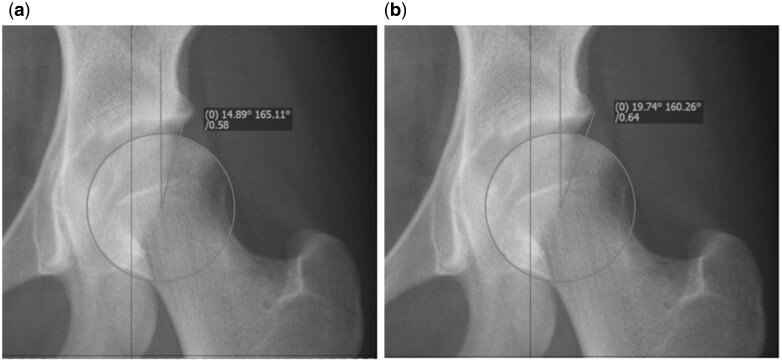

臨界髖關節(jié)發(fā)育不良BorderlineDDH(2):疼痛性臨界髖關節(jié)發(fā)育不良的治療作者:MichaelCWyatt,MartinBeck.作者單位:KlinikfürOrthop?dieundUnfallchirurgieLuzernerKantonsspital6004Luzern,Switzerland.譯者:陶可(北京大學人民醫(yī)院骨關節(jié)科)摘要在過去的幾十年里,影像技術的改進和手術技術的進步使得保髖手術得到了快速發(fā)展。然而,疼痛性臨界髖關節(jié)發(fā)育不良的治療仍然存在爭議。在這篇評論中,我們將確定相關問題并描述患者評估和治療方案。我們將提供自己的建議,并確定未來的研究領域。簡介在過去的幾十年里,髖關節(jié)生物力學知識的提高和手術技術的進步使得保髖手術得到了快速發(fā)展。保髖手術適應范圍廣泛,從髖臼淺且不穩(wěn)定的髖關節(jié)到髖臼深且患有股骨髖臼撞擊(FAI)的髖關節(jié)。雖然人們普遍認為,不穩(wěn)定髖關節(jié)發(fā)育不良的最佳治療方法是重新定位髖臼以增加覆蓋范圍,但人們同樣認為,必須減小過度覆蓋的髖臼臨界以消除撞擊。所有這些髖關節(jié)都可能存在凸輪畸形,需要在手術矯正時加以解決[1]。在最極端的情況下,所需的治療是顯而易見的。然而,有一個過渡區(qū),很難區(qū)分不穩(wěn)定性和股骨髖臼撞擊(FAI)。過去,這些髖關節(jié)被稱為“臨界”髖關節(jié)。通常,這包括外側中心臨界(LCE)角度在20°到25°之間的髖關節(jié)[2]。然而,“臨界”一詞是有問題的,因為它是一個放射學定義,只涉及描述髖關節(jié)穩(wěn)定性的幾個重要參數(shù)之一。髖臼頂傾斜角、前后覆蓋和股骨前傾是應納入髖關節(jié)穩(wěn)定性分析的其他因素。髖關節(jié)發(fā)育不良與髖關節(jié)骨關節(jié)炎之間的關聯(lián)已經(jīng)確定[3,4],有不穩(wěn)定跡象的髖關節(jié)發(fā)育不良退化速度更快[5]。臨界髖關節(jié)可能不穩(wěn)定、撞擊或兩者兼而有之。臨界髖關節(jié)發(fā)育不良的穩(wěn)定性很難確定,并且容易受個人主觀影響,骨科界普遍傾向于低估不穩(wěn)定性,從而導致不適當?shù)闹委?。最近的研究表明,對患有臨界發(fā)育不良(LCEA?>?20°)的患者進行關節(jié)鏡髖關節(jié)手術(包括盂唇修復和關節(jié)囊折疊縫合術)可能會在短期內(nèi)帶來適當?shù)母纳芠3,4]。然而,有證據(jù)表明,之前錯誤的髖關節(jié)鏡檢查會對此類髖關節(jié)的治療結果產(chǎn)生負面影響[6]。因此,疼痛性臨界髖關節(jié)發(fā)育不良的治療仍然是一個極具爭議的問題。臨界性髖關節(jié)發(fā)育不良在患有髖關節(jié)疼痛的年輕人中很常見,在選定的患者群中報告的患病率為37.6%[7]。在臨界髖關節(jié)發(fā)育不良中,可能與其他不穩(wěn)定原因(如韌帶松弛癥)有顯著重疊[8]。然而,根本問題是難以正確分類潛在的病理生物力學。定義第一個問題在于定義。在前后位骨盆X線片[9](LCEA)上測量的Wiberg外側中心邊緣角傳統(tǒng)上用于將髖關節(jié)分類為正常(LCEA?>25°)、發(fā)育不良(LCEA?<20°)或臨界(LCEA20–25°),盡管這些定義值在文獻中差異很大[3,10]。然而,使用外側中心邊緣角(LCEA)存在兩個問題。首先是測量方法。為了測量外側中心邊緣角(LCEA),首先通過與股骨頭輪廓相符的圓來定義股骨頭的中心。角度的第一個分支垂直穿過旋轉中心。第二個分支由股骨頭的中心和股骨最外側點定義(圖1a)。重要的是不要使用髖臼的最外側點(圖1b),因為這不符合Wiberg的定義,并且會給出錯誤的高值(外側中心邊緣角(LCEA)偏大)[11]。Fig.1.(a)CorrectmeasurementoftheLCEAusingtheedgeofthesourcil,indicatingmoderatedysplasia.(b)IncorrectmeasurementoftheLCEAinthesamehip.Usingthisvaluewouldfalselyclassifythishipasborderline.圖1(a)使用髖臼臨界正確測量外側中心邊緣角(LCEA),表明中度髖關節(jié)發(fā)育不良。(b)同一髖關節(jié)的外側中心邊緣角(LCEA)測量不正確。使用此值會錯誤地將此髖關節(jié)歸類為臨界。其次,實際術語“臨界髖關節(jié)發(fā)育不良”是由Wiberg本人首次提出的,包括外側中心邊緣角(LCEA)在20°和25°之間的髖關節(jié)[2]。外側中心邊緣角(LCEA)是一種放射學測量,本身無法預測臨界髖關節(jié)發(fā)育不良的穩(wěn)定性,也無法完全描述股骨頭覆蓋范圍。因此,外側中心邊緣角(LCEA)無法指導手術決策[12–14]。部分原因是外側中心邊緣角(LCEA)本身無法涵蓋發(fā)育不良的精確位置,并且忽略了前后股骨頭覆蓋范圍。此外,髖臼指數(shù)(AI)和股骨前傾等其他參數(shù)也與髖關節(jié)穩(wěn)定性密切相關。如果外側中心邊緣角(LCEA)減少,AI可能正常,在這種情況下很難評估髖關節(jié)的穩(wěn)定性[15]。另一方面,股骨前傾過度可能會加劇髖關節(jié)前部不穩(wěn)定[16]。根本問題是什么?對于疼痛的臨界髖關節(jié)發(fā)育不良,很難僅通過二維射線測量將病理機制表征為撞擊(穩(wěn)定)或發(fā)育不良(不穩(wěn)定),尤其是僅由髖臼功能決定而不考慮股骨的測量。髖關節(jié)穩(wěn)定性的功能表征對于指導手術決策至關重要。不穩(wěn)定髖關節(jié)從邏輯上可以從髖臼重新定向截骨術中受益,而穩(wěn)定髖關節(jié)可以從撞擊手術(如股骨凸輪骨成形術)中受益。那么關于髖關節(jié)內(nèi)病理學的了解有多少?應該如何評估這些患者?有哪些治療方案?手術結果如何?這組患者的潛在隱患是什么?未來的發(fā)展方向是什么?在這篇敘述性綜述文章中,我們旨在解決這些問題,并闡明這組具有挑戰(zhàn)性的患者的處理方法。髖關節(jié)發(fā)育不良和臨界髖關節(jié)不穩(wěn)定的潛在病理是什么?髖關節(jié)發(fā)育不良患者的關節(jié)接觸壓力異常增高,股骨頭(軟骨損傷,導致軟骨下)骨質相對暴露。髖臼通常較淺且前傾,盂唇經(jīng)常有代償性增大,但同時伴有髖臼后傾的情況也很高[17]。股骨通常呈外翻,前傾度高[10]。這些異常的解剖特征會導致病理性髖關節(jié)生物力學,表現(xiàn)為盂唇撕裂、軟骨損傷和髖關節(jié)不穩(wěn)定,這些很容易被誤解為撞擊。由于骨穩(wěn)定性受損,軟組織穩(wěn)定器(即纖維軟骨盂唇和髖關節(jié)囊)的重要性就凸顯出來[18]。一旦軟組織約束失效,髖關節(jié)就會變得不穩(wěn)定。然而,我們必須明白,主要的潛在病理是缺乏骨性穩(wěn)定性,這會導致髖關節(jié)失效,而不是軟組織穩(wěn)定性失效。半脫位髖關節(jié)發(fā)育不良的自然病史預后非常差,并且必然會導致關節(jié)退化[5]。惡化速度與半脫位嚴重程度和患者年齡直接相關,通常在癥狀出現(xiàn)后約10年,就會出現(xiàn)嚴重的退行性變化[19]。在沒有半脫位的情況下,自然病史很難預測退化速度。臨界髖關節(jié)發(fā)育不良也是如此。最近的一項研究強調(diào)了髖臼覆蓋的重要性。在一項為期20年的大型女性隊列研究中,研究顯示,如果外側中心邊緣角(LCE)低于28°,則每降低一度,放射學OA風險就會增加13%[20]。因此,除了短期緩解癥狀外,還必須考慮長期可能的發(fā)展。臨床表現(xiàn)臨界髖關節(jié)發(fā)育不良的臨床表現(xiàn)與其他年輕活躍成人髖關節(jié)疾?。ㄈ鏔AI綜合征[21])非常相似,因此,徹底的病史、體格檢查和放射學評估對于正確診斷這些患者至關重要。病史重點記錄病史。臨界髖關節(jié)發(fā)育不良患者的主要癥狀是疼痛。這通常發(fā)生在腹股溝和髖關節(jié)外側,但也可能發(fā)生在臀部(臀后區(qū))。有必要記錄完整的疼痛病史。尋找特定的不穩(wěn)定和“避免疼痛”癥狀,這可能表明已經(jīng)達到因缺乏骨性穩(wěn)定性而需要的軟組織代償?shù)臉O限。咔嗒聲和卡住的癥狀也很常見。此外,還會詢問患者是否有任何跡象表明患者已經(jīng)患上髖關節(jié)炎,例如夜間疼痛。癥狀應結合患者的功能限制和已經(jīng)接受的醫(yī)療護理,包括物理治療、藥物、其他意見和手術。檢查隨后應進行髖關節(jié)的合理臨床檢查,包括恐懼試驗和撞擊測試?;颊咄ǔ憩F(xiàn)出“膝內(nèi)翻”步態(tài),同時伴有髖關節(jié)內(nèi)收肌力矩增加和髖關節(jié)內(nèi)旋增加,這與股骨前傾增加一致。為了功能性地增加前覆蓋,可能存在前凸過度。應確定大轉子處有無壓痛[22]。務必記住檢查患者的旋轉輪廓、進行神經(jīng)血管檢查以及檢查全身關節(jié)松弛的跡象,并使用Beighton評分對此進行量化。具體關鍵目標包括排除(i)晚期退化過程的存在,例如表現(xiàn)為固定屈曲畸形和運動范圍減少,以及(ii)其他病理,例如腰椎病或L5神經(jīng)根病引起的疼痛。調(diào)查診斷成像應從骨盆的標準化AP平片和股骨頸側位片(穿桌側位、Dunn位、假斜位)[23]開始。仔細檢查這些圖像以測量LCEA、AI、擠壓指數(shù)、股骨頸干角和FEAR指數(shù)(見下文)。應確定骨關節(jié)炎的Tonnis等級以及是否存在凸輪形態(tài)。應仔細檢查不穩(wěn)定的直接跡象,這些跡象包括股骨頭移位,可通過與髂坐線的距離增加、Shenton線斷裂和AP視圖上股骨頭重新定位來識別,髖關節(jié)處于外展狀態(tài),使用MR關節(jié)造影時后關節(jié)間隙中有釓,這表明股骨頭向前移位,因此不穩(wěn)定。FEAR指數(shù)與不穩(wěn)定性有很高的相關性(見下文)。必須精確測量和記錄各種參數(shù)。有必要使用三維計算機斷層掃描(CT)進行橫斷面成像,以獲得有關骨解剖結構和發(fā)育不良位置的精確信息,包括髖關節(jié)周圍囊腫的存在和位置[24-26]。此外,CT還應包括股骨前傾的評估,如果前傾過大,可能會加劇髖關節(jié)前部不穩(wěn)定。磁共振成像(MR-關節(jié)造影)應遵循專門的髖關節(jié)檢查方案,包括徑向圖像采集或重建和關節(jié)內(nèi)造影劑應用[27],以檢查關節(jié)內(nèi)結構和盂唇和關節(jié)軟骨的病理??梢詤^(qū)分引起類似癥狀的其他原因,例如缺血性壞死、轉子滑囊炎或臀肌病變。其他測量包括盂唇大小[13,28]和髂關節(jié)囊體積[29]。對于這些患者,我們還提倡進行非牽引性MR關節(jié)造影檢查,以檢查是否存在釓積聚,即所謂的“新月征”,這是軸向視圖上不穩(wěn)定的細微征兆[30]。這些測量值的價值是什么?在平片上,那些直接表明不穩(wěn)定的測量值是股骨頭移位,與髂坐線的距離增加,Shenton線斷裂,髖關節(jié)外展時AP視圖上股骨頭重新定位,以及FEAR指數(shù)。在MR關節(jié)造影中,后下關節(jié)間隙中釓的存在表明股骨頭移位,因此不穩(wěn)定。AI、NSA、AT、高髂囊體積和盂唇體積可能存在增加,但不能預測不穩(wěn)定性[30](表1)。表1.用于評估髖關節(jié)不穩(wěn)定性的各種參數(shù)概述TheFemoro-EpiphysealAcetabularRoof(FEAR)index:股骨骨骺髖臼頂指數(shù)Thefemoralneck-shaftangle(NSA):頸干角FEAR指數(shù)是最近描述的參數(shù),似乎對預測髖關節(jié)穩(wěn)定性具有很高的價值[27]。它是由髖臼頂與股骨生長板中央1/3處之間的角度形成的(圖2)。其依據(jù)是:在生長過程中,股骨的骨骺生長板會垂直于髖關節(jié)的關節(jié)反作用力。股骨頸的生長和方向受股骨頸下生長板的控制[31]。Pauwels和Maquet[32]提出理論,合力作用于骨骺軟骨的中心,在生長過程中,根據(jù)Heuter-Volkman原理,骨骺板會垂直于關節(jié)反作用力。Pauwels和Maquet的理論后來得到了Carter等人[33]的證實,他們通過二維有限元分析研究了髖關節(jié)負荷的影響。閉合的骨骺板的角度表示跨股骨近端骨骺[34]的力的平衡,也表示跨關節(jié)力在過去的作用方式。因此,它是一個功能參數(shù),反映了髖關節(jié)在生長過程中長期的關節(jié)反作用力。如果FEAR<0°,則認為髖關節(jié)穩(wěn)定。統(tǒng)計分析表明,5°的臨界值預測穩(wěn)定性的概率為80°。最近的研究表明,2°的臨界值預測穩(wěn)定性的概率為90%(Batailler等人,正在準備發(fā)表中)。使用FEAR指數(shù)的案例如圖3a和b所示。Fig.2.TheFEARindex.Theangleismeasuredbetweenalineconnectingthemostmedialandlateralpointofthesourcilandalineconnectingthemedialandlateralendofthestraightpart(usuallycentralthird)ofthephysealscarofthefemoralhead.AnegativeFEARindex,withtheangleopeningmediallyasshowninFig.3a,indicatesastablehip.圖2.?FEAR指數(shù)。測量連接股骨最內(nèi)側和外側點的線與連接股骨頭骨骺直線部分(通常為中央三分之一)內(nèi)側和外側端的線之間的角度。如圖3a所示,角度向內(nèi)側打開的陰性FEAR指數(shù),表示髖關節(jié)穩(wěn)定。Fig.3.(a)CaseexamplesusingtheFEARindex.17-year-oldmale,LCEA20°,FEAR0°.Hipdeemedthereforestableandpatientmanagedwithhiparthroscopy.(b)CaseexamplesusingtheFEARindex.17-year-oldfemale,LCEA20°,FEAR8°.HipdeemedthereforeunstableandpatientmanagedwithPAO.圖3.(a)使用FEAR指數(shù)的病例。17歲男性,LCEA20°,F(xiàn)EAR0°。因此髖關節(jié)穩(wěn)定,患者接受髖關節(jié)鏡治療。(b)使用FEAR指數(shù)的病例。17歲女性,LCEA20°,F(xiàn)EAR8°。因此髖關節(jié)不穩(wěn)定,患者接受PAO截骨治療。有哪些治療方案?治療取決于髖關節(jié)的穩(wěn)定性。疼痛性臨界髖關節(jié)發(fā)育不良的治療方案包括非手術治療、解決關節(jié)內(nèi)撞擊的手術治療(通過髖關節(jié)鏡或髖關節(jié)外科脫位進行的FAI手術)和解決不穩(wěn)定性的手術治療(采用PAO和/或股骨截骨術的重新定位截骨術)(見圖2)。非手術治療包括患者教育、活動調(diào)整、簡單的止痛藥、非甾體抗炎藥和髖關節(jié)腔內(nèi)注射藥物[35]。有針對性的物理治療可以改善肌肉調(diào)節(jié)、疼痛和本體感受控制。以下段落將討論包括關節(jié)鏡和/或截骨術的臨界髖關節(jié)發(fā)育不良的手術治療方案。這組患者接受髖關節(jié)鏡檢查的結果如何?隨著髖關節(jié)鏡技術的最新發(fā)展,許多外科醫(yī)生正在使用它來治療臨界髖關節(jié)發(fā)育不良,尤其是因為人們認為髖臼周圍截骨術等替代技術的風險更高,術后恢復時間更長。臨界髖關節(jié)發(fā)育不良的髖關節(jié)鏡檢查還可以讓外科醫(yī)生處理髖關節(jié)內(nèi)病變,如盂唇撕裂或股骨凸輪畸形[3,12,36]。如果考慮使用PAO來解決骨穩(wěn)定性不足的問題,那么關節(jié)鏡檢查不僅可以讓外科醫(yī)生了解髖關節(jié)的關節(jié)內(nèi)狀態(tài),還可以了解患者在隨后進行更大規(guī)模手術時的表現(xiàn)[37]。然而,關于臨界髖關節(jié)發(fā)育不良的髖關節(jié)鏡檢查的已發(fā)表文獻很少,而且短期隨訪也存在局限性。在Jo等的系統(tǒng)綜述中,確定了13項關于髖關節(jié)發(fā)育不良的關節(jié)鏡檢查的研究[10]。這些研究各不相同,所有研究都是病例系列。僅有6項研究報告了主觀和/或客觀結果。關節(jié)鏡檢查的手術指征不明確,患者事先接受過多種非手術治療。此外,臨界髖關節(jié)發(fā)育不良的確切定義各不相同,只有兩項研究使用了Byrd和Jones的定義[36]。三項研究報告了髖關節(jié)鏡作為輔助工具,三項研究報告了髖關節(jié)鏡作為獨立治療。盂唇撕裂的總患病率為77.3%,主要位于髖臼緣的前部或前上部。髖臼軟骨病變比股骨病變更常見(59-75.2%比11-32%),并且位于盂唇病變的鄰近。僅有兩項研究檢查了臨界髖關節(jié)發(fā)育不良病例(LCEA20-25°)的關節(jié)鏡檢查結果,其中只有一項描述了患者報告的結果測量。后者是Byrd和Jones[36]的前瞻性臨床病例系列,其中66%的髖關節(jié)(32髖)患有臨界髖關節(jié)發(fā)育不良。關節(jié)鏡檢查后,平均改良Harris髖關節(jié)評分從50(差)改善到77(一般)。作者得出結論,髖關節(jié)鏡治療可能解決髖關節(jié)內(nèi)病理而不是發(fā)育不良的放射學證據(jù)的結果。對臨界髖關節(jié)發(fā)育不良進行髖關節(jié)鏡檢查有什么危險?臨界髖關節(jié)發(fā)育不良患者進行關節(jié)鏡盂唇切除術和髖臼外側緣切除術可導致爆發(fā)性髖關節(jié)不穩(wěn)定[38]。即使修復了盂唇,也必須保留髂股韌帶和髖關節(jié)的其他靜態(tài)穩(wěn)定器,以防止不可逆的后果或導致髖關節(jié)不穩(wěn)定[39–41]。沒有確鑿的文獻支持在這些情況下進行關節(jié)囊修復,但這似乎是一種安全合理的做法[42]。關節(jié)囊復位技術可提高臨界髖關節(jié)發(fā)育不良的穩(wěn)定性[12]。如果髖關節(jié)在術前足夠不穩(wěn)定,那么僅通過髖關節(jié)鏡治療關節(jié)內(nèi)病變是不夠的,患者將需要進行PAO截骨術[43,44]。必須記住,髖關節(jié)的穩(wěn)定性首先取決于髖骨幾何形狀。在輕微不穩(wěn)定(臨界發(fā)育不良)中,穩(wěn)定性可能由次級軟組織結構來確保。一旦這些結構因微創(chuàng)傷或大創(chuàng)傷而失效,髖關節(jié)就會變得不穩(wěn)定?;謴蛙浗M織穩(wěn)定性可能只會在短時間內(nèi)改善髖關節(jié)穩(wěn)定性,但軟組織很可能再次磨損。因此,必須首先解決潛在的骨病理問題,才能取得良好的長期效果。最近的一份報告顯示,髖關節(jié)發(fā)育不良患者在髖關節(jié)鏡檢查失敗后,PAO的髖關節(jié)特定功能結果較差[6]。因此,對這組患者單獨進行髖關節(jié)鏡檢查應謹慎處理。但是,對于那些由于髖關節(jié)狀況不佳(即AI和股骨前傾正常)或高齡(即>40歲)而不適合進行PAO的患者,它可能有用。重新定向髖臼周圍截骨術對這組患者有何影響?通過髖臼周圍截骨術進行髖臼重新定向已成為髖關節(jié)發(fā)育不良最常見的治療方法,據(jù)報道術后20多年效果良好。傳統(tǒng)上,PAO時關節(jié)內(nèi)病變的處理方法是進行前關節(jié)切開術。然而,隨著PAO微創(chuàng)技術的發(fā)展,情況已不再如此。微創(chuàng)PAO技術縮短了術后恢復時間[45]。最近的一項研究表明,一些可改變的因素,例如較高的體力活動量和較高的BMI(大于30kg/m2)可導致PAO的發(fā)病年齡下降[46]。此外,患有較重發(fā)育不良程度的患者患PAO的年齡也較早:LCEA是手術年齡的獨立預測因素,即LCEA較低的患者往往需要在較早的年齡接受PAO手術。但是,輕度和中度發(fā)育不良患者的PAO預后沒有差異。在本研究中,輕度發(fā)育不良被歸類為15-25°,這涵蓋了我們對臨界髖關節(jié)發(fā)育不良的定義。最近的一項多中心前瞻性隊列研究檢查了患者報告的PAO結果指標,結果表明,雖然總體結果良好,但臨界髖關節(jié)發(fā)育不良患者和男性的改善程度低于發(fā)育較重的患者[47]。作者討論了小范圍矯正的危險,這可能導致過度矯正和醫(yī)源性FAI、股骨前傾增加和軟組織松弛。建議和未來方向在臨界髖關節(jié)中,關鍵步驟是確定穩(wěn)定性。關于髖關節(jié)的穩(wěn)定性,只有兩種情況:髖關節(jié)穩(wěn)定或不穩(wěn)定。沒有中間狀態(tài)。如果接受這個概念,治療就會變得相對簡單。不穩(wěn)定可能與其他病癥(如FAI或超負荷/過度使用和軟骨疾病)相結合,需要同時治療。如果髖關節(jié)不穩(wěn)定,則需要髖臼重新定位。僅解決磨損的二級穩(wěn)定器并不能解決潛在的生物力學問題,最多只能產(chǎn)生令人滿意的短期結果。在穩(wěn)定的髖關節(jié)中,可以進行開放或關節(jié)鏡關節(jié)保留手術。然而,我們必須記住,低于28°的LCE角度每減少一度,骨關節(jié)炎的發(fā)病率就會增加13%[20]。因此,如果有疑問,為了最大限度地提高獲得良好長期結果的機會,我們主張進行髖臼重新定向PAO截骨手術。重要的是要確定我們?nèi)狈χR的領域,以指導進一步的研究。將對這些患者進行長期隨訪研究,比較髖臼重新定向和髖關節(jié)鏡檢查,理想情況下,將記錄所有成像參數(shù)和Beighton評分。此外,還應獲得患者報告的結果測量和恢復時間,以及包括運動在內(nèi)的活動恢復時間。?TheFEARindexisarecentlydescribedparameterthatseemstohaveahighvaluetopredictstabilityofthehip[27].Itisformedbytheanglebetweentheacetabularroofandthecentralthirdofthefemoralgrowthplate(Fig.2).Itisbasedonthefactthatduringgrowththeepiphysealgrowthplateofthefemurorientsitselfperpendicularlytothejointreactingforcesofthehip.Growthandtheorientationofthefemoralneckareunderthecontrolofthesubcapitalgrowthplate[31].PauwelsandMaquet[32]theorizedthattheresultantforceactsfromthecenteroftheepiphysealcartilageandthatduringgrowth,theepiphysealplateorientsitselfperpendiculartothejointreactionforceinaccordancewiththeHeuter–Volkmanprinciple.PauwelsandMaquet’stheorylaterwasconfirmedbyCarteretal.[33]whostudiedtheinfluenceofhiploadingbybi-dimensionalfiniteelementanalysis.Theangleoftheclosedepiphysealplateindicatesthebalanceofforcesacrosstheproximalfemoralphysis[34]andindicateshowthetransarticularforcesactedinthepast.Therefore,itisafunctionalparameterthatreflectsthejointreactingforcesoveralongperiodoftimeduringgrowthofthehip.IftheFEARis?<0°thehipisconsideredstable.Statisticalanalysishasshownthatacutoffvalueof5°predictsstabilitywith80°probability.Morerecentworkhasshownthatacutoffvalueof2°predictsstabilitywith90%probability(Batailleretal.,inpreparation).CaseexamplesofusingtheFEARindexareshowninFig.3aandb.ThemanagementofthepainfulborderlinedysplastichipAbstractImprovedimagingandtheevolutionofsurgicaltechniqueshavepermittedarapidgrowthinhippreservationsurgeryoverthelastfewdecades.Themanagementofthepainfulborderlinedysplastichiphoweverremainscontroversial.Inthisreview,wewillidentifythepertinentissuesanddescribethepatientassessmentandtreatmentoptions.Wewillprovideourownrecommendationsandalsoidentifyfutureareasforresearch.INTRODUCTIONImprovedknowledgeabouthipbiomechanicsandtheevolutionofsurgicaltechniqueshavepermittedarapidgrowthinhippreservationsurgeryoverthelastfewdecades.Thespectrumcoversawiderangefromhipswithshallowacetabuli,whichareunstable,tohipswithdeepacetabulithataresufferingfromfemoro-acetabularimpingement(FAI).Whilethereisageneralagreementthatthebesttreatmentfortheunstabledysplastichipisareorientationoftheacetabulumtoincreasecover,thereisequalagreementthattherimoftheover-coveringacetabulumhastobereducedtoremoveimpingement.Onallthosehipsacamdeformitymaybepresentthatneedstobeaddressedatthetimeofsurgicalcorrection[1].Atthefarendsofthespectrumtherequisitetreatmentisobvious.However,thereisatransitionzonewhereitisdifficulttodiscriminateinstabilityfromFAI.Inthepastthesehipswerereferredtoas‘borderline’hips.Usually,thisincludedhipswithalateralcenteredge(LCE)anglebetween20°and25°[2].However,theterm‘borderline’isproblematic,becauseitisaradiographicdefinitionandonlyaddressesoneofseveralparametersimportanttodescribehipstability.Acetabularroofobliquity,anteriorandposteriorcoverandfemoralantetorsionareotherfactorsthatshouldbeincludedintoananalysisofhipstability.Theassociationofhipdysplasiawithhiposteoarthritisisestablished[3,4]anddysplastichipswithsignsofinstabilitydegenerateatahigherrate[5].Aborderlinehipcaneitherbeunstable,impingingormaybeboth.Thestabilityoftheborderlineisdifficulttodetermineandsubjecttointerpretationwithageneraltendencyintheorthopaediccommunitytounderestimateinstabilitythatthenleadstoinappropriatetreatment.Recentstudiessuggestthatarthroscopichipsurgerywithlabralrepairandcapsularplicationinpatientswithborderlinedysplasia(LCEA?>?20°)mayresultinappropriateshort-termimprovements[3,4].However,thereisevidencethatawronglydoneprevioushiparthroscopyhasanegativeimpactontheoutcomeonthetreatmentofsuchhips[6].Therefore,themanagementofthepainfulborderlinedysplastichiphoweverremainsanissueofgreatcontroversy.Borderlinehipdysplasiaiscommoninyoungadultswithhippainwithareportedprevalenceof37.6%inselectedpatientcohorts[7].Intheborderlinedysplastichiptheremaybesignificantoverlapwithothercausesofinstabilitysuchasconnectivetissuelaxity[8].However,thefundamentalissueisthedifficultyincorrectlyclassifyingtheunderlyingpatho-biomechanics.DEFINITIONThefirstproblemliesinthedefinition.TheLateralCentreEdgeAngleofWibergasmeasuredonanAntero-posteriorpelvicradiograph[9](LCEA)hastraditionallybeenusedtoclassifyhipsasnormal(LCEA?>25°),dysplastic(LCEA?<20°)orborderline(LCEA20–25°)althoughthesedefiningvaluesvarywidelyintheliterature[3,10].However,theuseoftheLCEAhastwoproblems.Firstlythemethodbywhichitshouldbemeasured.TomeasuretheLCEAthecenterofthefemoralheadisfirstdefinedbyacirclefittingthecontourofthefemoralhead.Thefirstbranchoftheanglerunsperpendicularthroughthecenterofrotation.Thesecondbranchisdefinedbythecenterofthefemoralheadandthemostlateralpointofthesourcil(Fig.1a).Itisimportantnottousethemostlateralpointoftheacetabulum(Fig.1b),becausethisdoesnotfollowthedefinitionofWiberg,andwillgivefalsehighvalues[11].Secondlytheactualterm‘Borderlinehipdysplasia’wasfirstintroducedbyWiberghimself,includinghipswithaLCEAbetween20°and25°[2].LCEAisaradiographicmeasureandpersecannotpredictstabilityintheborderlinedysplastichipnordoesfullydescribefemoralheadcoverage.ThereforetheLCEAcannotdirectsurgicaldecisionmaking[12–14].PartofthereasonisthatLCEAalonedoesnotencompassthepreciselocationofdysplasiaanddisregardsanteriorandposteriorfemoralheadcoverage.Alsootherparameterssuchasacetabularindex(AI)andfemoralantetorsionareveryrelevantforstabilityofthehip.InthepresenceofadecreasedLCEAAImaybenormalinwhichcasethestabilityofthehipisdifficulttoassess[15].Ontheotherhand,excessivefemoralanteversionmaypotentiateanteriorhipinstability[16].WHATISTHEFUNDAMENTALISSUE?Inthepainfulborderlinedysplastichipitisdifficulttocharacterizethepathologicalmechanismasimpingement(stable)ordysplasia(unstable)byatwo-dimensionalradiographicmeasurementalone,especiallyonethatissolelyafunctionoftheacetabulumandtakesnoaccountofthefemur.Thisfunctionalcharacterizationofhipstabilityisofparamountimportancetoguidesurgicaldecision-making.Anunstablehipwouldlogicallybenefitfromacetabularreorientationosteotomywhilstastablehipwouldbenefitfromimpingementsurgerysuchasfemoralcamosteoplasty.Sowhatisknownabouttheintra-articularpathology?Howshouldthesepatientsbeassessed?Whatarethetreatmentoptions?Whatarethesurgicaloutcomes?Whatarethepotentialpitfallswiththisgroupofpatients?Whatarethefuturedirections?Inthisnarrativereviewarticleweaimtoaddressthesequestionsandelucidatethemanagementofthischallenginggroupofpatients.WHATISTHEUNDERLYINGPATHOLOGYOFHIPDYSPLASIAANDUNSTABLEBORDERLINEHIPS?Inhipdysplasia,thereareabnormallyhigharticularcontactpressuresandrelativebonyuncoveringofthefemoralhead.Theacetabulumistypicallyshallowandantevertedwithanoftencompensatoryenlargedlabrum,butthereisalsoahighprevalenceofconcomitantacetabularretroversion[17].Thefemurisclassicallyinvalguswithhighantetorsion[10].Theseabnormalanatomicalfeaturescausepathologicalhipbiomechanicswhichmanifestaslabraltears,chondrallesions,andhipinstability,whichcaneasilybemisinterpretedasimpingement.Astheosseousstabilityiscompromisedtheimportanceofthesofttissuestabilisers,namelythefibrocartilaginouslabrumandthehipcapsule,isaccentuated[18].Oncethesofttissueconstraintsfailthenthehipbecomesunstable.However,onehastounderstandthattheprincipalunderlyingpathologyisthelackofosseousstability,whichleadstofailureofthehipandnotthefailingsofttissuestability.Thenaturalhistoryofthesubluxingdysplastichipisaverypoorprognosisandinvariablyleadstojointdegeneration[5].Therateofdeteriorationisdirectlyrelatedtosubluxationseverityandpatientageandusuallyabout10?yearsafteronsetofsymptomsseveredegenerativechangeshavedeveloped[19].Thenaturalhistoryintheabsenceofsubluxationismoredifficulttopredictconcerningthespeedofdegeneration.Thesameaccountsforborderlinedysplastichips.Arecentstudyhighlightstheimportanceofacetabularcover.Inalargecohortoffemales,followedfor20?years,itwasshownthateachdegreereductioninLCEbelow28°isassociatedwith13%increasedriskofradiographicOA[20].Therefore,besidesshort-termreliefofsymptoms,thelong-termpossibleevolutionhastobekeptinmind.CLINICALPRESENTATIONTheclinicalpresentationofborderlineacetabulardysplasiaisverysimilartothatofotheryoungactiveadulthipdisorders,suchasFAIsyndrome[21]soathoroughhistory,physicalexamination,andradiographicevaluationareessentialtoproperlydiagnosethesepatients.HISTORYAfocusedhistoryistaken.Theprimarysymptominpatientswithborderlinehipdysplasiaispain.Thisistypicallyperceivedingroinandlateralhipbutcanalsobeinthebuttock.Afullpainhistoryiswarranted.Particularsymptomsofinstabilityand‘givingway’aresoughtthatmayindicatethatthelimitsofsofttissuecompensationforalackofosseousstabilityhavebeenreached.Symptomsofclickingandcatchingarealsocommon.Furthermoreanyindicationsthatthepatienthasestablishedhiparthritis,suchasnightpain,areaskedfor.Thesymptomsshouldbeputintothecontextofthepatient’sfunctionallimitationsandmedicalattentionalreadyreceivedincludingphysiotherapy,medications,otheropinionsandsurgery.EXAMINATIONAlogicalclinicalexaminationofthehipshouldfollowincludingapprehensionandimpingementtests.Thepatientwilloftendisplaya‘kneeing-in’gaitinassociationwithanincreasedhipadductormomentandincreasedinternalhiprotationconsistentwithincreasedfemoralantetorsion.Hyperlordosismaybepresentinordertofunctionallyincreaseanteriorcover.Tendernessoverthegreatertrochantershouldbedetermined[22].Itiscrucialtoremembertoexaminethepatient’srotationalprofile,performaneurovascularexaminationandtocheckforsignsofgeneralizedjointlaxityandquantifythisusingBeighton’sscore.Specifickeyaimsincluderefutingthepresenceof(i)anadvanceddegenerativeprocessmanifestforexamplewithfixedflexiondeformityanddecreasedrangeofmotionand(ii)alternativepathologysuchaspainreferredfromlumbarspondylosisorL5radiculopathy.INVESTIGATIONSDiagnosticimagingshouldcommencewithstandardizedplainAPradiographofthepelvisandalateralfemoralneckviews(lateralcrosstable,Dunnview,falseprofileviews)[23].TheseimagesarescrutinizedtomeasuretheLCEA,AI,extrusionindex,femoralneck-shaftangleandFEARindex(seebelow).TheTonnisgradeofosteoarthritisshouldbedeterminedalongwithwhetherthereiscammorphology.Directsignsofinstabilityshouldbescrutinizedforandthesecomprisefemoralheadmigration,recognizedbyanincreaseddistancefromtheilioischialline,abreakinShenton’slineandrecenteringofthefemoralheadonanAPviewwiththehipinabductionandGadoliniumintheposteriorjointspacewhenusingMR-arthrography,thatindicatesanteriormigrationandthusinstabilityofthefemoralhead.TheFEARindexhasahighassociationwithinstability(seebelow).Thevariousparametershavetobemeasuredpreciselyandrecorded.Cross-sectionalimagingwiththree-dimensionalcomputerizedtomography(CT)forpreciseinformationonbonyanatomyandlocationofdysplasiaincludingthepresenceandlocationofperiarticularcystsiswarranted[24–26].FurthermoreCTshouldincludeestimationoffemoralantetorsionwhich,ifhighmaypotentiateanteriorhipinstability.Magneticresonanceimaging(MR-arthrography)shouldfollowadedicatedprotocolfortheexaminationofthehip,includingradialimageacquisitionorreconstructionandintra-articularapplicationofcontrast[27]toexamineforintra-articularstructuresandpathologyofbothlabrumandarticularcartilage.Othercausesforsimilarsymptomssuchasavascularnecrosis,trochantericbursitisorglutealpathologycanbedifferentiated.Additionalmeasurementsincludelabralsize[13,28]andiliocapsularisvolume[29].Inthesepatients,wealsoadvocatenon-tractionMRarthrographytoexamineforaaccumulationofgadoliniumknownasa‘crescentsign’whichisasubtlesignofinstabilityontheaxialview[30].WHATISTHEVALUEOFTHESEMEASUREMENTS?Onplainfilmsthosemeasurementsthataredirectsignsofinstabilityarefemoralheadmigrationwithanincreaseofthedistancefromtheilioischialline,abreakinShenton’slineandrecenteringofthefemoralheadontheAPviewwithhipsinabductionandtheFEARindex.OnMR-arthrographythepresenceofGadoliniuminthepostero-inferiorjointspaceindicatesmigrationofthefemoralheadandthusinstability.TheAI,NSA,AT,highiliocapsularisvolumeandincreasedlabralvolumemaybepresentbutarenotpredictiveofinstability[30](Table1).WHATARETHETREATMENTOPTIONS?Treatmentdependsonthestabilityofthehip.Thetreatmentalternativesforthepainfulborderlinedysplastichipincludenon-operativetreatment,surgicaltreatmenttoaddressintra-articularimpingement(FAIsurgerybyeitherhiparthroscopyorsurgicalhipdislocation)andsurgicaltreatmenttoaddressinstability(reorientationosteotomywithPAOand/orfemoralosteotomy)(seeFig.2).Non-operativemanagementincludespatienteducation,activitymodification,simpleanalgesics,non-steroidalanti-inflammatorymedications,andintra-articularinjections[35].Targetedphysiotherapycanimprovemuscularconditioning,painandproprioceptivecontrol.Thesurgicaltreatmentoptionsfortheborderlinedysplastichipwhichcomprisearthroscopyand/orosteotomywillbediscussedinthefollowingparagraphs.WHATARETHERESULTSOFHIPARTHROSCOPYINTHISGROUPOFPATIENTS?Withtherecentevolutioninhiparthroscopymanysurgeonsareusingthistoaddressborderlinedysplastichips,notleastbecauseofperceivedhigherrisksandlongerpost-operativerecoveryassociatedwithalternativetechniquessuchasperiacetabularosteotomy.Hiparthroscopyinborderlinedysplastichipspermitsthesurgeontoaddressintra-articularpathologysuchasalabraltearorfemoralcamdeformity[3,12,36].IfPAOisbeingconsideredtoaddresstheinadequatebonystabilitythenarthroscopymaygivethesurgeonvaluableinsightsnotonlyintotheintra-articularstatusofthehipbutalsohowthepatientislikelytofarewithamuchlargersubsequentoperation[37].However,thereislittlepublishedliteratureonhiparthroscopyinborderlinedysplastichipsandwhatthereislimitedbyshort-termfollow-up.InthesystematicreviewbyJoetal.,13studieslookingatarthroscopyindysplastichipswereidentified[10].Thestudieswereheterogeneousandallstudieswerecaseseries.Onlysixstudiesreportedonsubjectiveand/orobjectiveoutcomes.Thesurgicalindicationsforarthroscopywereambiguousandpatientshadreceivedvariablenon-operativemanagementapriori.FurthermoretheprecisedefinitionofborderlinehipdysplasiavariedandonlytwostudiesusedthedefinitionofByrdandJones[36].Threestudiesreportedonhiparthroscopyasanadjuvanttoolandthreeasastand-alonetreatment.Labraltearshadanoverallprevalenceof77.3%andtheseweremostlylocatedintheanteriororanterosuperiorportionoftheacetabularrim.Acetabularchondrallesionsweremorecommonthanfemorallesions(59–75.2%versus11–32%)andlocatedadjacenttothatofthelabralpathology.Therewereonlytwostudiesthatexaminedtheoutcomesofarthroscopyinborderlinehipdysplasticcases(LCEA20–25°)ofwhichonlyonedescribedpatientreportedoutcomemeasures.Thelatter,aprospectiveclinicalcaseseriesbyByrdandJones[36],had66%ofhips(32hips)withborderlinedysplasia.ThemeanmodifiedHarrisHipscoreimprovedfrom50(poor)to77(fair)followingarthroscopy.Theauthorsconcludedthatthetreatmentresponseislikelyafunctionofaddressingtheintra-articularpathologyratherthantheradiographicevidenceofdysplasia.WHATARETHEDANGERSWITHDOINGHIPARTHROSCOPYINBORDERLINEDYSPLASTICHIPS?Arthroscopiclabralresectionandremovaloflateralacetabularriminborderlinehipdysplasiacanleadtofulminantjointinstability[38].Evenifthelabrumisrepaireditisimperativetopreservetheiliofemoralligamentandotherstaticstabilizersofthehiptopreventtheirreversibleconsequencesorrenderingthehipunstable[39–41].Thereisnoconclusiveliteraturetosupportcapsularrepairinthesecasesbutthisseemsasafeandsensiblepractice[42].Capsularreductiontechniquestoimprovestabilityhavebeendescribedinborderlinedysplastichips[12].Ifthehipissufficientlyunstablepre-operativelythenaddressingtheintra-articularpathologyalonebyhiparthroscopywillbeinsufficientandthepatientwillrequireaPAO[43,44].Onehastobearinmindthatstabilityofthehipfirstlinedependsontheosseousgeometry.Insubtleinstability(borderlinedysplasia)stabilitymaybesecuredbysecondarysofttissuestructures.Oncethesefailduetomicro-ormacrotraumathehipbecomesunstable.Restoringsofttissuestabilitymayimprovehipstabilityforashortperiodoftimeonly,butitislikelythatthesofttissueswearoutagain.Thereforetheunderlyingosseouspathologyhastobeaddressedfirsttoachievegoodlong-termresults.ArecentreportshowedaninferiorhipspecificfunctionaloutcomeofPAOafterfailedhiparthroscopyinhipdysplasia[6].Hiparthroscopyaloneinthisgroupofpatientsshouldbethereforeapproachedwithcaution.However,itmayhavearoleinthosepatientswhoareeitherunsuitableforPAOeitherbecausetheirhipsareunfavourable(i.e.haveanormalAIandnormalfemoralanteversion)orbecausetheiradvancedage(i.e.>40years).WHATARETHERESULTSOFREORIENTINGPERIACETABULAROSTEOTOMYINTHISGROUPOFPATIENTS?Acetabularreorientationviatheperiacetabularosteotomyhasbecomethemostcommontreatmentforacetabulardysplasiawithgoodoutcomesreportedatover20?yearspostoperatively.Traditionallyintra-articularpathologywasaddressedatthetimeofPAObyperformingananteriorarthrotomy.HoweverwiththedevelopmentofminimallyinvasivetechniquesforPAOthisisnolongernecessarilythecase.LessinvasivePAOtechniqueshavedecreasedthetimetopostoperativerecovery[45].ArecentstudyshowedmodifiablefactorssuchashigherphysicalactivityandhigherBMIgreaterthan30?kg/m2leadtoadecreasedageofpresentationforPAO[46].FurthermorepatientsalsopresentedearlierforPAOwithworsedegreesofdysplasia:theLCEAwasindependentlypredictiveofageatsurgery,i.e.patientswithalowerLCEAtendedtorequirePAOsurgeryatanearlierage.However,therewasnodifferenceinoutcomesfollowingPAObetweenmildandmoderatedysplasia.Inthisstudymilddysplasiawasclassifiedas15–25°whichencompassesourdefinitionofborderlinehipdysplasia.Arecentmulticenterprospectivecohortstudythatexaminedpatient-reportedoutcomemeasuresofPAOshowedthat,althoughoverallresultsweregood,improvementsinborderlinehipdysplasticsandmaleswerelessthaninthosepatientswhohadmoreseveredysplasia[47].TheauthorsdiscussedthiswiththedangerofasmallcorrectionthatmayleadtoovercorrectionandiatrogenicFAI,increasedfemoralantetorsionandsofttissuelaxity.RECOMMENDATIONSANDFUTUREDIRECTIONSInborderlinehipsthecrucialstepistodefinestability.Regardingthestabilityofthehipthereareonlytwoconditions:Thehipiseitherstableorunstable.Thereisnothinginbetween.Ifthisconceptisaccepted,thetreatmentgetscomparablysimple.InstabilitymaybecombinedwithotherpathologieslikeFAIoroverload/overuseandcartilagediseasewhichneedconcomitanttreatment.Ifthehipisunstable,acetabularreorientationisnecessary.Addressingonlywornoutsecondarystabilizersdoesnotsolvetheunderlyingbiomechanicproblemandatbestwillyieldsatisfactoryshorttermresults.Instablehips,openorarthroscopicjointpreservingsurgerymaybeperformed.However,wehavetokeepinmindthateachdegreedecreaseoftheLCEanglebelow28°isassociatedwitha13%increaseofosteoarthrosis[20].Therefore,ifindoubt,inordertomaximizethechanceofgoodlong-termresults,wewouldadvocateforanacetabularreorientationoperation.Itisimportanttoidentifytheareaswherewelackknowledgeinordertoguidefurtherresearch.Longer-termfollow-upstudiescomparingacetabularreorientationandhiparthroscopyinthesepatients,ideallyinwhichallimagingparametersandBeightonscoresarerecordedwouldbeperformed.Inadditionpatient-reportedoutcomemeasuresandtimetorecoveryandresumptionofactivitiesincludingsportshouldbeattained.文獻出處:MichaelCWyatt,MartinBeck.Themanagementofthepainfulborderlinedysplastichip.ReviewJHipPreservSurg.2018Apr5;5(2):105-112.doi:10.1093/jhps/hny012.